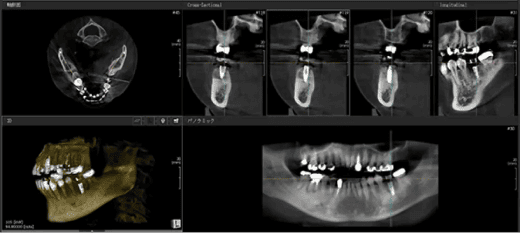

インプラント治療をご希望の方には、レントゲンやCT、型取りなど、各種検査を行います。

治療計画の作成と設計

患者さま一人ひとりに合わせて、最適な治療計画をご提案します。

顎の骨に人工歯根を埋め込みます。事前にシミュレーションを行い、その通りに治療を進めるためのガイドを作成しますので、ご安心ください。